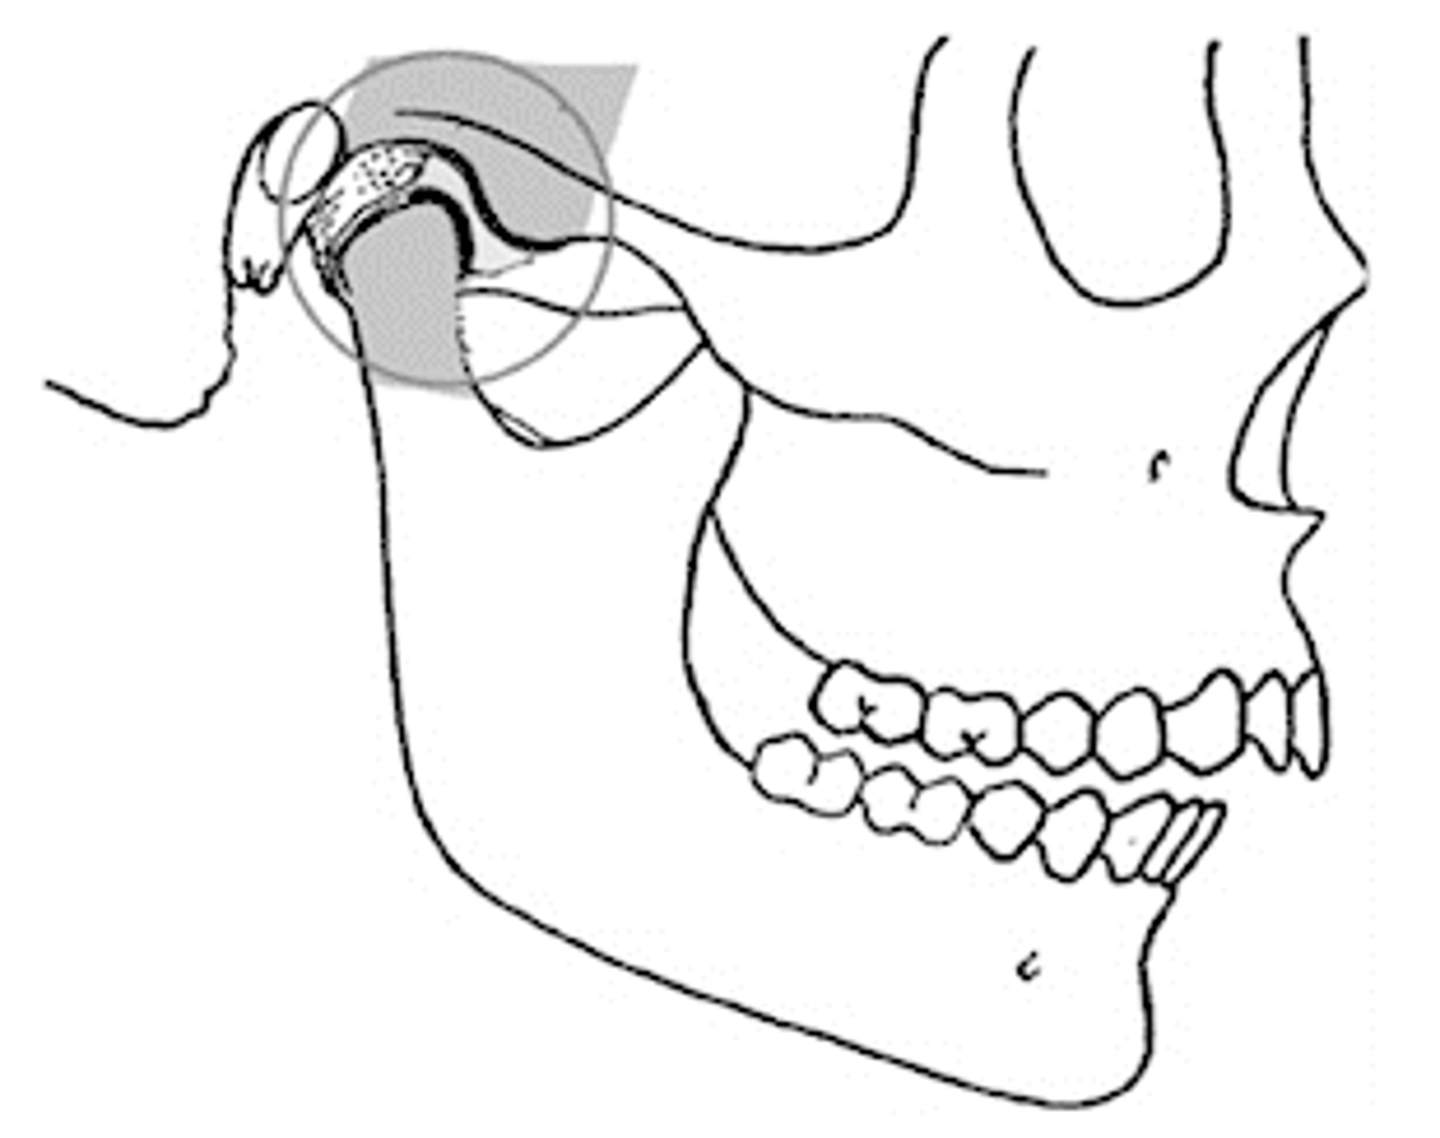

Centric Relation (CR)

maxillomandibular relationship where the functional heads of the condyles are in the most unrestrained, retruded anatomic position in the glenoid fossae of the temporomandibular joints

<p>maxillomandibular relationship where the functional heads of the condyles are in the most unrestrained, retruded anatomic position in the glenoid fossae of the temporomandibular joints</p>

What is independent on tooth contacts (meaning only based on joint)?

centric relation